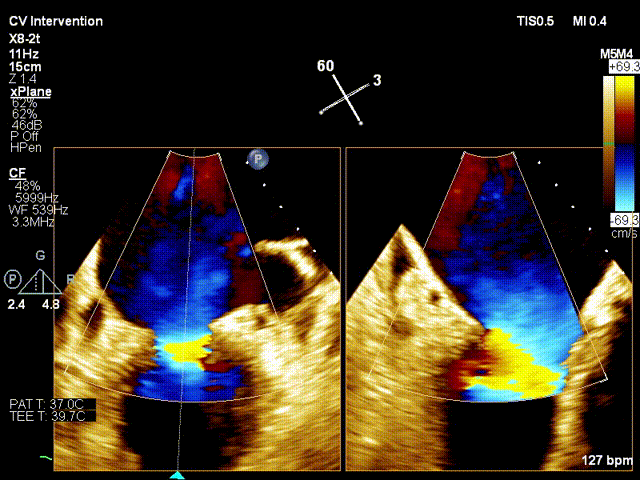

术前xPlane view提示:二尖瓣重度反流

术后xPlane view提示:二尖瓣反流显著减少